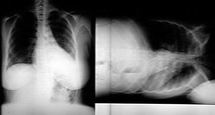

Aortic Disruption

left Bronchus depressed

left pleural Effusion

widened Mediastinum

apical Cap

Aortic knob indistinct

Trachea deviated to right